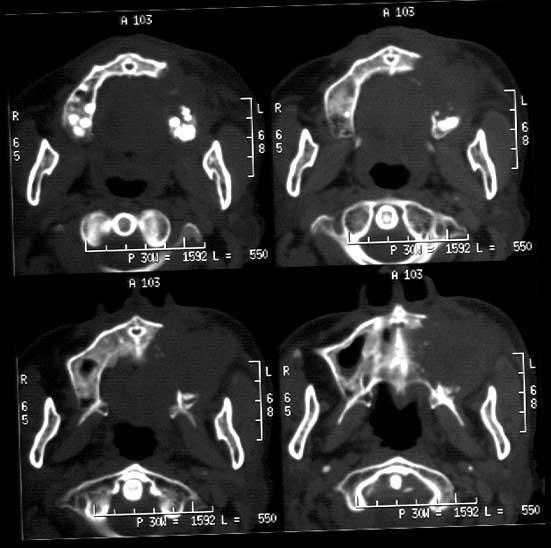

典型右侧上颌窦癌1例